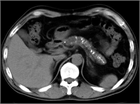

1. 膵管内の結石(膵石)を認めた場合と、膵全体に分布する複数かつびまん性の石灰化を認めた場合は慢性膵炎と診断できる(推奨度1)

1. 加齢現象に伴い膵石が観察される場合がある。

1. 石灰化を伴った膵腫瘍がまれに存在する。